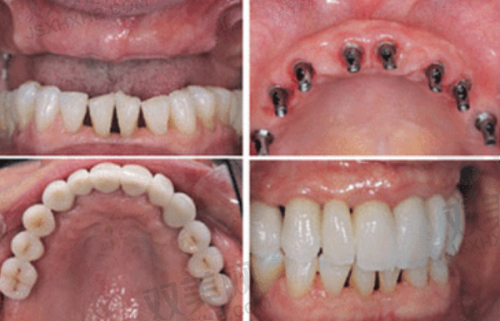

2. **牙齿种植**:采用精良的种植技术和优质的种植体,为缺失牙患者提供安心、有效的种植修复方案,修复牙齿的咀嚼功能和美观。

2. **个性化治疗方案**:医生会根据每个患者的口腔状况、需求和期望,制定个性化的治疗方案。在牙齿正畸方面,会综合考虑患者的牙齿排列、咬合关系、面部形态等因素,选择更适合的矫正方法;在牙齿种植方面,会根据患者的牙槽骨条件、缺失牙情况等,选择合适的种植体和种植方案。这种个性化的治疗方案能够更好地满足患者的需求,提高治疗成效。

3. **优质的材料**:医院在治疗过程中使用的都是优质的口腔材料,如正畸托槽、种植体、牙齿美白剂等。这些材料具有良好的生物相容性和稳定性,能够确保治疗的安心性和有效性。例如,种植体采用的是国内外有名品牌的产品,具有良好的骨结合能力,能够确保种植体的长期稳定;牙齿美白剂则是经过严格检测的安心产品,能够在不损伤牙齿的前提下达到理想的美白成效。